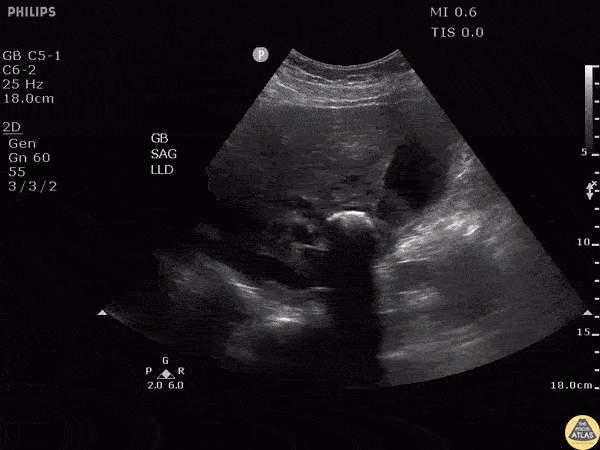

Biliary - Gallstone in Neck Causing Mirizzi's Syndrome

Note the hyperechoic structure with posterior acoustic shadowing indicative of a gallstone. Patient was moved and the stone remained lodged in the neck. Additionally, gallbladder sludge can be seen. The patient was found to have elevated LFTs. MRCP performed demonstrating external compression of biliary tree this large stone in GB neck consistent with Mirizzi’s syndrome. Image courtesy of Robert Jones DO, FACEP @RJonesSonoEM Director, Emergency Ultrasound; MetroHealth Medical Center; Professor, Case Western Reserve Medical School, Cleveland, OH View his original post here